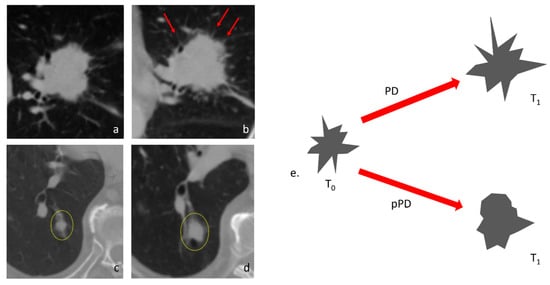

3.3. Features That Distinguish PD and Pseudo-Progression